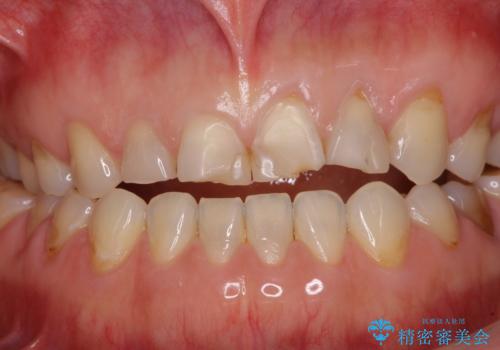

- 咬み合わせと度重なる応急処置の繰り返しにより、前歯がガタガタになってしまったとのことで来院された患者様です。

4本の前歯が気になっていたので、全てをオールセラミッククラウンにて補綴治療を行うこととしました。